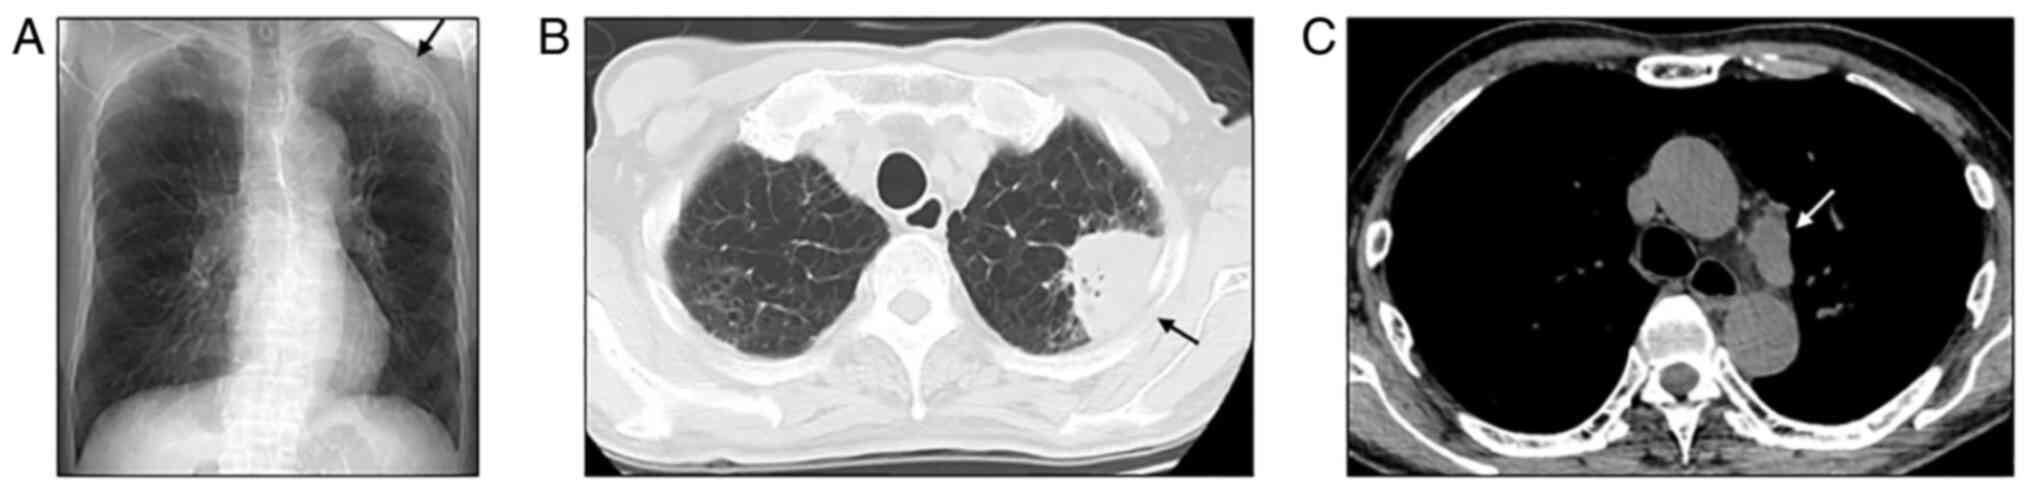

In March of Year X, the patient was admitted to Hino Municipal Hospital complaining of a walking disturbance. The patient was conscious, and his vital signs were intact. Neurological examination revealed unilateral spatial neglect and mild hemiparesis of the left extremities. Chest radiography and computed tomography revealed a primary lung tumor (maximum diameter, 60 mm) invading the chest wall in the left upper lobe and subaortic lymphadenopathy (Fig. 2A-C) without any other metastatic sites. Gadolinium-enhanced magnetic resonance imaging showed a solitary brain tumor in the right parietal lobe (maximum diameter, 40 mm) consisting of solid and cystic components (estimated cyst volume, 37.5 ml) (Fig. 3, reference group). A retrospective review of imaging examinations revealed that the lung tumor was 20 mm in diameter, and brain metastasis was absent 1 year ago. Cyst aspiration of the BM followed by surgical resection or stereotactic irradiation was recommended for the rapid control of neurological symptoms. The patient underwent placement of an Ommaya reservoir catheter, and 7 ml of bloody-yellowish aspirate was collected, in which cohesive pleomorphic malignant cells were detected. Unfortunately, the catheter collapsed early, resulting in insufficient tumor shrinkage. While catheter replacement or surgical resection of the BM were treatment options, split gamma knife (GK) was performed to minimize the patient's therapeutic burden and allow an earlier initiation of immunotherapy. A twice-split GK was performed with a prescription dose to tumor margin of 14 Gy each, resulting in a shrinkage of the solid portion and reduction in cyst volume by 62.2 and 23.0% following the first and second rounds of GK, respectively (Fig. 3). During the period of GK treatment, the patient's neurological symptoms improved to the point where he was able to walk independently and was discharged from the hospital. In July of Year X, the patient started anti-PD-1 immunotherapy (pembrolizumab, 400 mg intravenous administration, every 6 weeks). After two cycles of treatment, substantial regression was observed in the primary tumor and a mediastinal lymph node, thereby indicating a partial response (Fig. 3). In addition, the solitary compartment of the brain metastasis disappeared, and the cyst volume further decreased by 18.4% during this period. Skin eruption and adrenal deficiency appeared after the first and sixth cycles of pembrolizumab treatment, respectively, and were treated appropriately. The patient is currently continuing pembrolizumab for 12 cycles and has maintained progression-free survival. The patient did not complain of any neurological or physical symptoms.

Figure 2.

Radiological images in March of Year X. (A) Chest radiograph showing a tumor in the left upper field (arrow). Chest computed tomography showing (B) a primary lung tumor located in the left upper lobe (arrow) with (C) subaortic mediastinal lymph node metastasis (arrow).